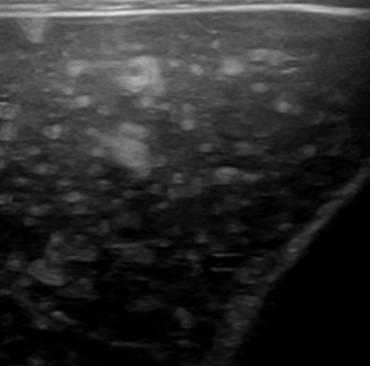

Hamartoma đường mật

» Thông tin: Nam giới – 39 tuổi.

» Lâm sàng: Kiểm tra sức khỏe.